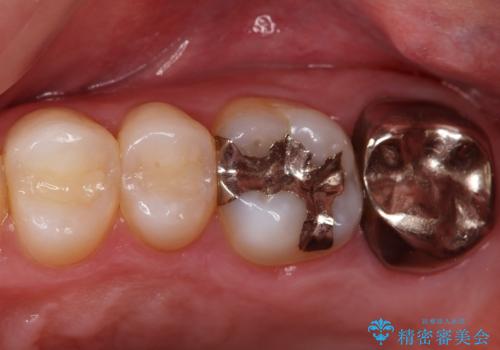

- 歯茎がよく腫れ、痛みが出ることを主訴に来院された患者様です。

レントゲン等から、金属の被せ物が歯にあって作られていないことがわかり、汚れの貯留もみられました。

金属を除去し、虫歯の治療後に型取りを行い、清掃性、審美性に優れたセラミックインレー、セラミッククラウンを装着いたしました。